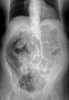

Trauma with colonic perforation

Gastrointestinal perforation, also known as ruptured bowel, is a hole in the wall of part of the gastrointestinal tract. The gastrointestinal tract includes the esophagus, stomach, small intestine, and large intestine. [Source: Wikipedia ]